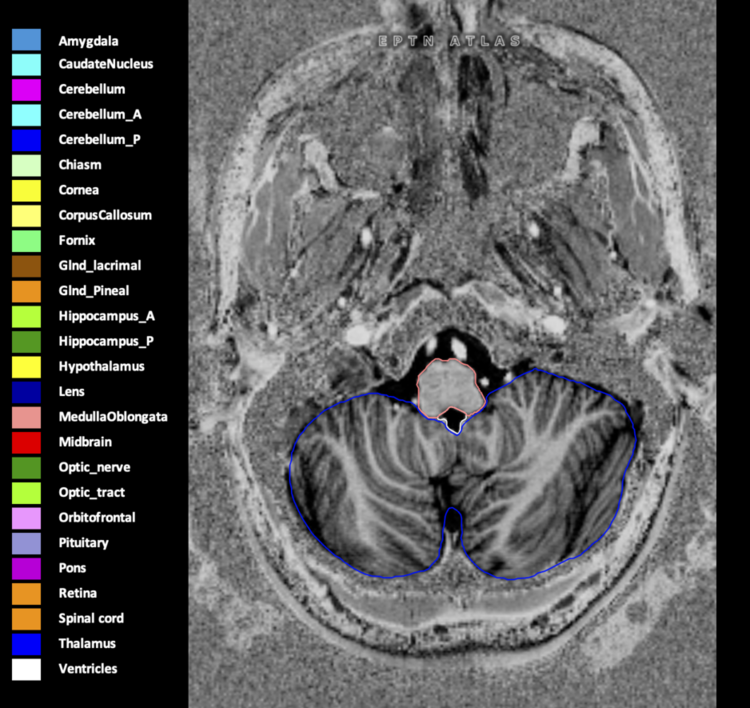

Eekers et al. have published an international neurological atlas for contouring of organs at risk in consensus with the European Particle Therapy Network (EPTN) in 2018 and an update in 2021. The purpose of this consensus atlas is to decrease inter- and intra-observer variability in delineating OARs relevant for neuro-oncology.

Included are all OARs known to be relevant for radiation-induced toxicity in neuro-oncology: brain, brainstem (midbrain, pons, medulla oblongata), chiasm, cerebellum (anterior & posterior), cochlea, cornea, hippocampus (anterior & posterior), hypothalamus, lens, lacrimal gland, optic nerve, pituitary, skin, and vestibular & semicircular canals. To further facilitate research on cognition, vision and radiological changes after irradiation of the brain, potential clinically-relevant OARs are included: amygdala, caudate nucleus, cerebellum (anterior & posterior), corpus callosum, fornix, macula, optic tract, orbitofrontal cortex, periventricular space (PVS), pineal gland, and thalamus.

We propose this atlas is used in photon and particle therapy in order to derive consistent dosimetric data. When required this atlas will be updated according to new insights.

Three-dimensional delineation of the 25 consensus OARs for neuro-oncology are shown on CT (WW/WL 120/40, 3000/600), 3T MR images, (T1Gd, T2FLAIR 1mm) and 7T MR (MP2RAGE 0.7 mm). All are presented in transversal, sagittal and coronal view.